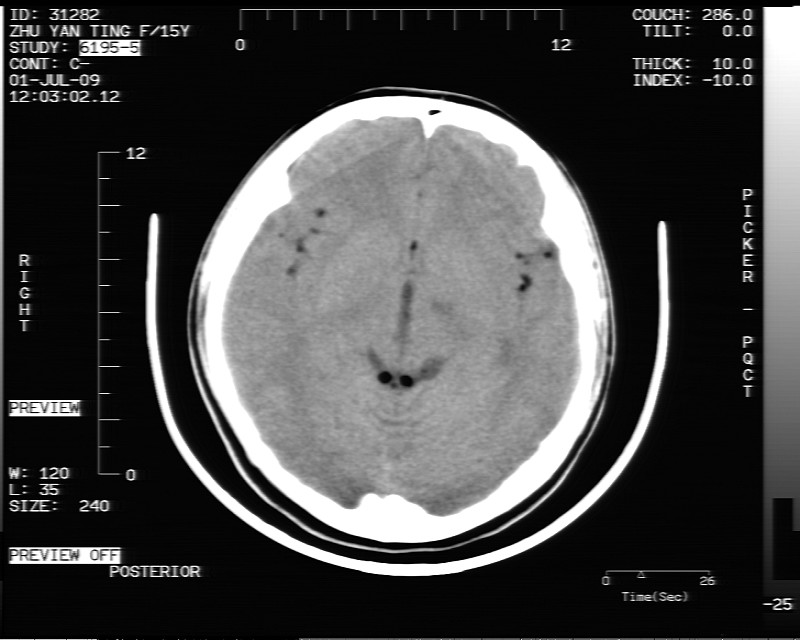

以下是引用随光逐影在2009-7-1 16:26:00的发言:[br]鞍上池表皮样囊肿或含脂肪类肿瘤破裂并化学性脑炎?

以下是引用余辉在2009-7-1 17:20:00的发言:[br]病变ct值-20至-80[br]考虑脑内脂肪瘤破裂,瘤主体应该在右侧桥小脑角池及鞍上池[br]鞍上池病灶面积较大,ct值应该能够测准,应此病灶应该就是脂肪密度,病灶密度有ct值-20至-80hu,为成熟脂肪密度,因此考虑脂肪瘤,也不除外其他含成熟脂肪的病灶[br]皮样囊肿密度应该稍高一点

以下是引用zjzjr在2009-7-1 16:52:00的发言:[br]支持皮样囊肿破裂.,表皮样囊肿一般密度均高.[br][br][本贴已被 zjzjr 于 2009-7-1 16:52:29 修改过]